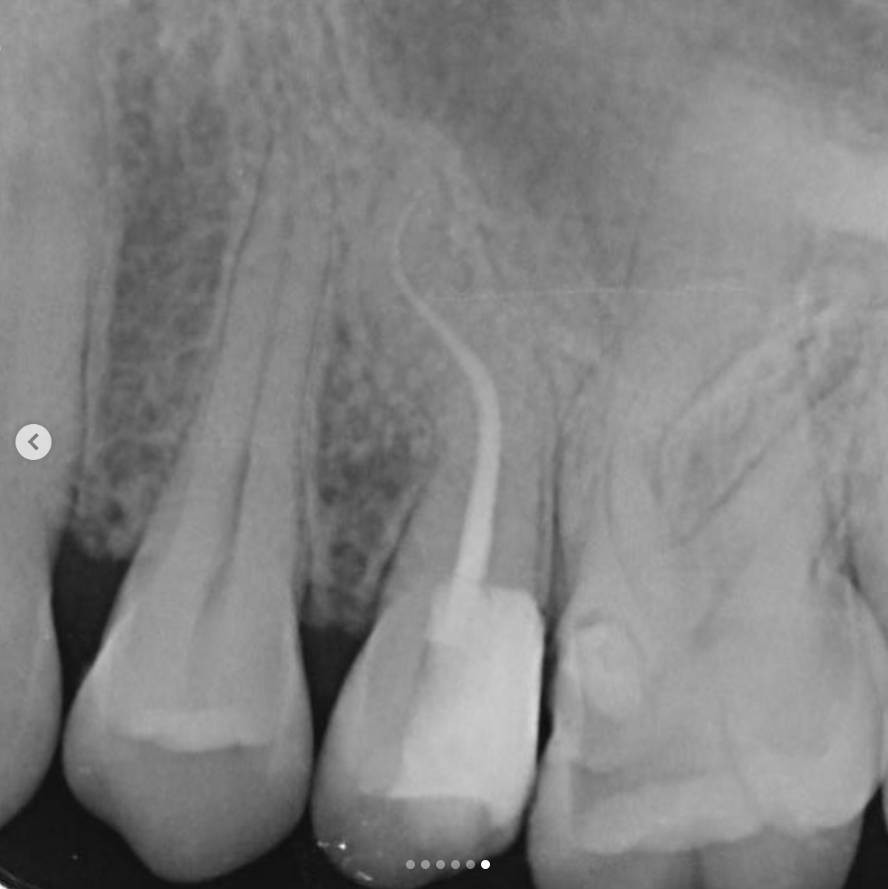

5. The treatment was completed in a single visit, using a bioceramic root canal sealer.

• The roots exhibit two curvatures, and although there are two canals, they converge at a single apical foramen.

4. A working length radiograph was taken with gutta-percha cones to confirm canal length.